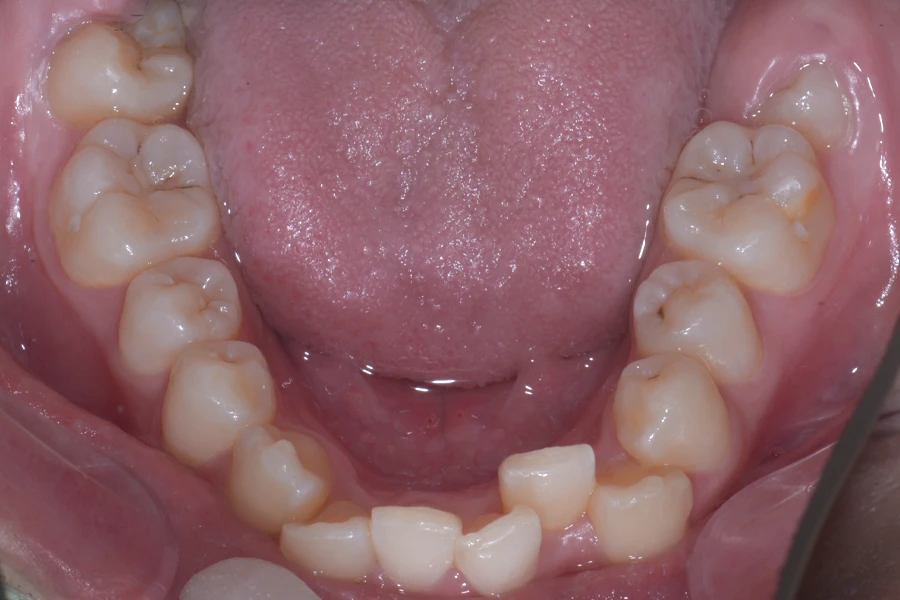

• 治療前

主訴 八重歯を治したい

治療内容 上下顎ラビアル矯正(表側矯正)